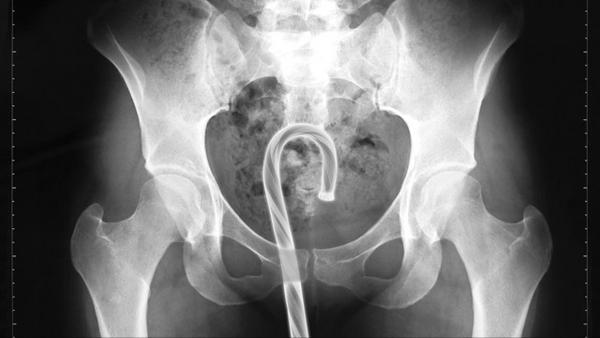

Man (88) arriveert in ziekenhuis met bom uit Eerste Wereldoorlog in anus![]()

Man (88) arriveert in ziekenhuis met bom uit Eerste Wereldoorlog in anus

Er was afgelopen zaterdag een bommelding in een ziekenhuis in Frankrijk toen een 88-jarige Fransman arriveerde met een twintig centimeter langewww.waterkant.net

Met oud en nieuw gaat ie een bompijl laten verdwijnen.